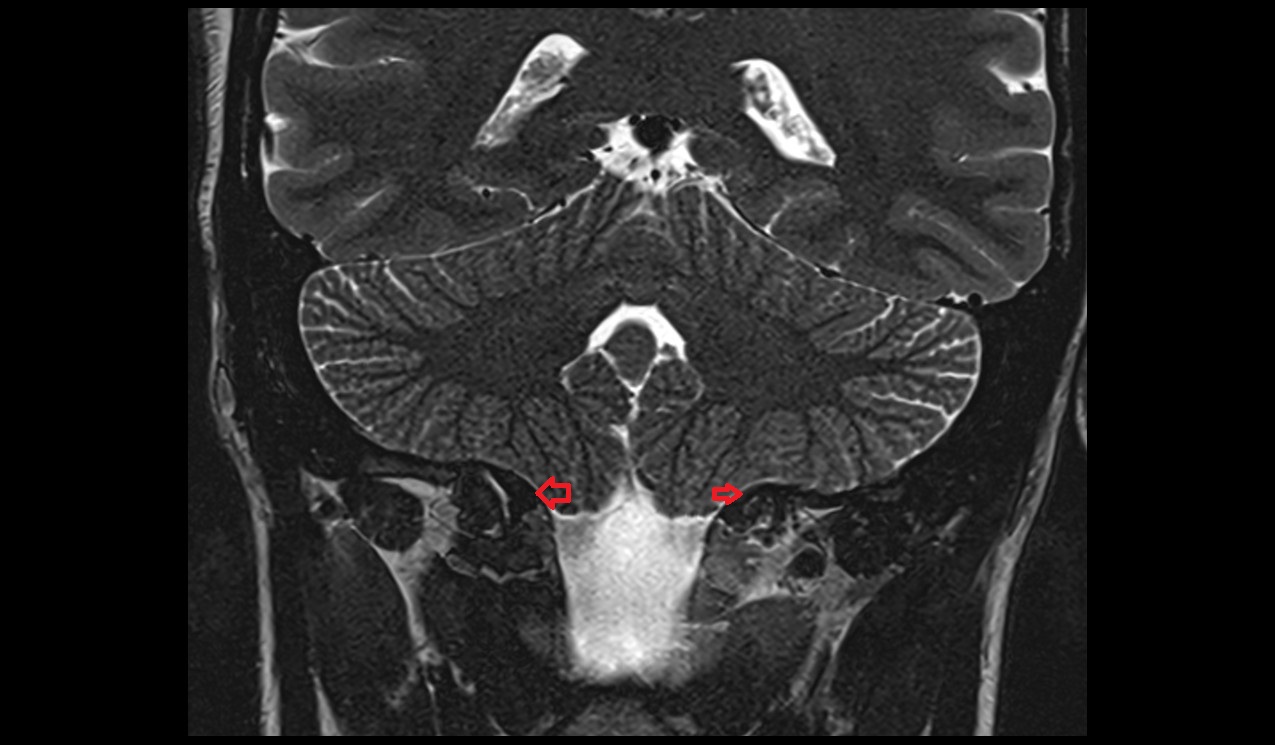

- Lateral aperture of fourth ventricle (foramen of Luschka)